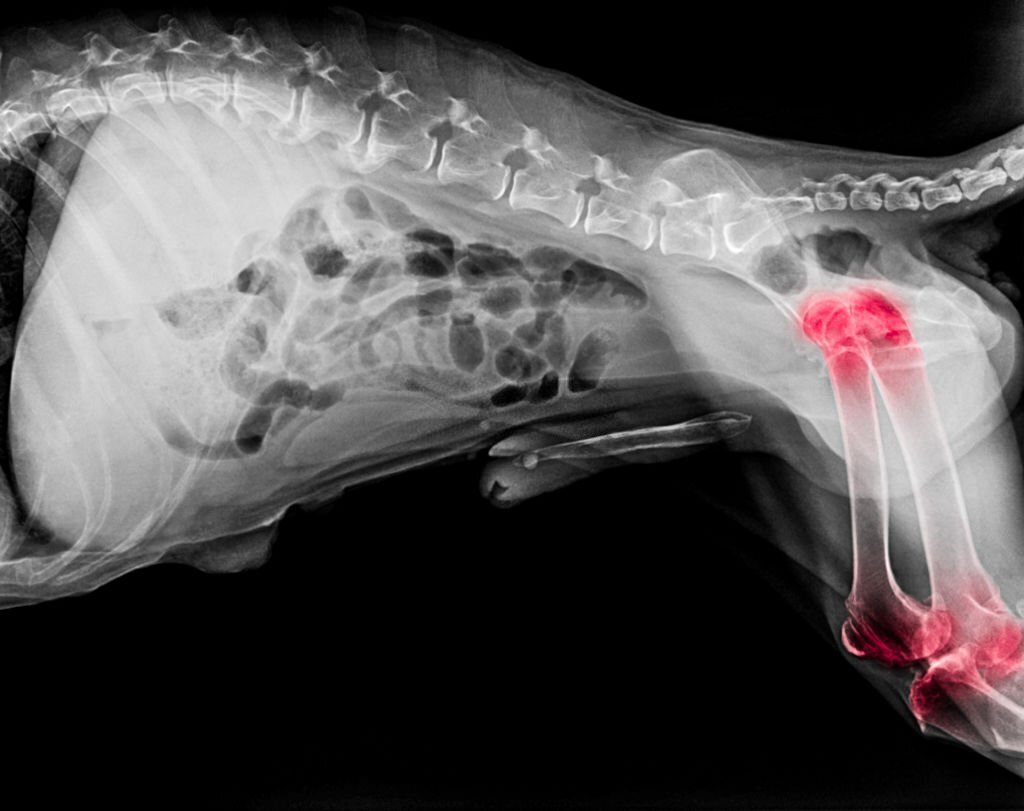

Bệnh xương khớp ở chó là một trong những vấn đề sức khỏe phổ biến nhất, đặc biệt ở chó trưởng thành và chó lớn tuổi. Khi hệ vận động suy yếu hoặc bị tổn thương, chó sẽ gặp khó khăn trong sinh hoạt và giảm chất lượng cuộc sống đáng kể. Việc hiểu rõ nguyên nhân, dấu hiệu và các phương pháp chăm sóc xương khớp chó giúp người nuôi chủ động hơn trong việc phòng ngừa và hỗ trợ điều trị.

Ngoài ra, yếu tố di truyền cũng góp phần không nhỏ, nhất là ở các giống như Golden Retriever, German Shepherd hay Labrador – những giống có nguy cơ cao mắc chứng loạn sản hông. Bên cạnh đó, tai nạn, té ngã, vận động sai tư thế hoặc chế độ ăn thiếu dưỡng chất hỗ trợ xương khớp cũng làm tăng nguy cơ bệnh.